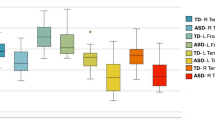

Two-way ANOVA revealed significant group differences for both faxon (p = .010) and Daxon (p = .045). As demonstrated in Fig. 2, the TD group had faxon and Daxon values higher than the ASD group, and the effect seemed to encompass all segments of the corpus callosum. Main effect of segment was also significant for all four diffusion metrics (p < .0001), suggesting varying diffusion properties across the five callosal segments. Post hoc analyses revealed differences between groups for faxon in callosal segments 2 to 5 and for Daxon in callosal segment 3. After correcting for multiple comparisons, group differences in segment 3 to 5 for faxon were found to be significant (Table 2). ADextra, RDextra, and the number of callosal voxels did not differ across groups. No significant between-group differences were noted in any of the traditional diffusion tensor metrics (Additional file 1: Figure S1).